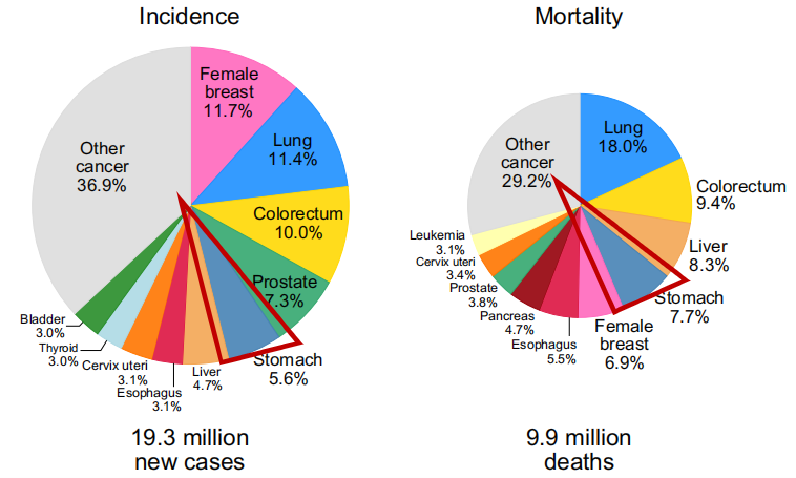

ж•°жҚ®жү№жіЁиғғзҷҢжӮЈиҖ…дёӯдҪҚжҖ»з”ҹж¶ҜзҺҮд»…дёә16дёӘжңҲ[2]�пјҢ�пјҢ�пјҢпјҢ еӣ иғғзҷҢж—©жңҹж— жҳҫзқҖз—ҮзҠ¶�пјҢ�пјҢ�пјҢпјҢеҜјиҮҙеӨ§йғЁеҲҶзЎ®иҜҠж—¶е·ІеёҢжңӣиҮідёӯжҷҡжңҹ�пјҢ�пјҢ�пјҢпјҢеёҢжңӣжңҹиғғзҷҢ5е№ҙз”ҹж¶ҜзҺҮд»…дёә30%пјҒжҲ‘еӣҪж—©жңҹиғғзҷҢиҜҠж–ӯзҺҮдҪҺдәҺ10%�пјҢ�пјҢ�пјҢпјҢиҝҷжҳҜиғғзҷҢеҸ‘з—…зҺҮе’Ңж®’е‘ҪзҺҮеұ…й«ҳдёҚдёӢзҡ„дё»иҰҒзјҳж•…еҺҹз”ұпјҒ

иӢҘж—©жңҹиғғзҷҢйў„еҗҺдјҳејӮ�пјҢ�пјҢ�пјҢпјҢ5е№ҙжҖ»з”ҹж¶ҜзҺҮиҫҫеҸҜ90%д»ҘдёҠ�гҖӮ�гҖӮжҺЁеҠЁиғғзҷҢзҡ„ж—©еҸ‘жҳҺгҖҒж—©иҜҠж–ӯгҖҒж—©жІ»з–—�пјҢ�пјҢ�пјҢпјҢеҜ№ж”№е–„жӮЈиҖ…йў„еҗҺз”ҹж¶Ҝжғ…еҪўеҫҲжҳҜдё»иҰҒ�пјҢ�пјҢ�пјҢпјҢеӣ жӯӨжҲ‘еӣҪдәҹеҫ…е»әи®ҫжңүз”Ёзҡ„ж Үи®°зү©зі»з»ҹе’Ңз”ЁдәҺеӨ§и§„жЁЎдәәзҫӨзӯӣжҹҘзҡ„жЈҖжөӢиҰҒйўҶд»Ҙйў„иӯҰиғғзҷҢзҡ„зҲҶеҸ‘�гҖӮ�гҖӮ